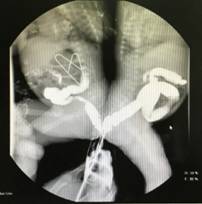

2005年,中山医院葛均波在世界上首次应用逆向导引钢丝技术